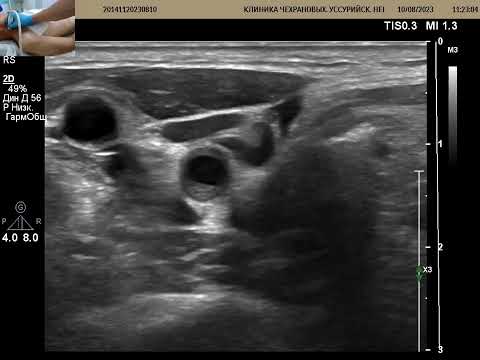

Лекция для врачей цикла первичной переподготовки по УЗД. Представляет общий обзор типов кривых скоростей кровотока основных сосудов организма. Запись 17.10.2020.